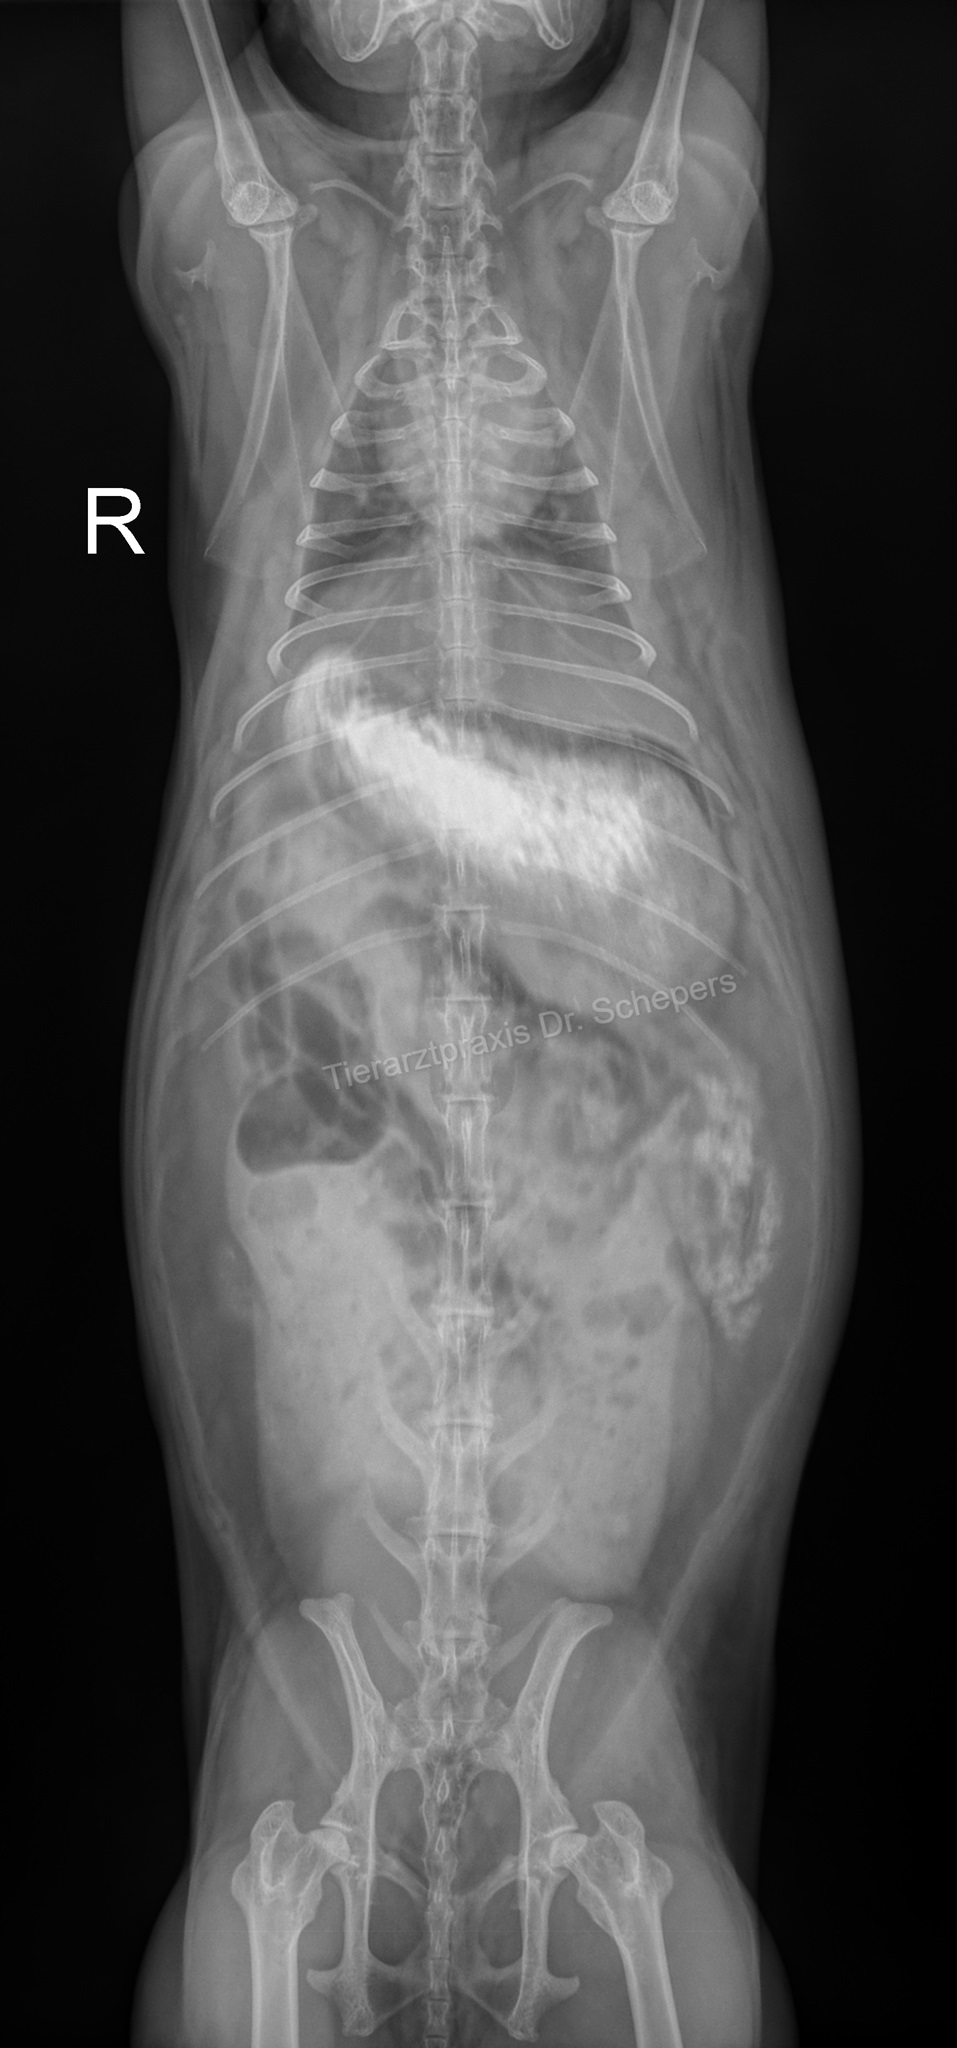

Röntgendiagnostik

Die sichere Diagnose wird durch ein Röntgenaufnahmen gestellt; hierdurch kann die Konsistenz des Mageninhalts (fest, flüssig, aufgegast) auch von weniger geübten Tierärzten sicher und objektiv beurteilt werden. Zudem besteht eine objektive Vergleichsmöglichkeit für spätere Verlaufskontrollen.

Weiterhin kann objektiv beurteilt werden, wie groß der Magen tatsächlich ist, wie lange der Zustand bereits besteht (beim mechanischen Ileus v. a. anhand der Konsistenz des Mageninhaltes: anfangs homogen, anschließend "spiegeleiartig" durch beginnende Gasbildung) sowie inwieweit eine Magentympanie (= Aufgasung) beteiligt ist. Ein gewöhnlicher Kaninchenmagen ist rund, mit homogenem, strukturiertem Inhalt gefüllt und ragt maximal zu einem Drittel über den Rippenbogen hinaus.

Auch kann die Füllung des Magen-Darm-Trakts bereits einen deutlichen Hinweis auf einen Darmverschluss liefern: Bei dem typischen, im vorderen Dünndarmbereich lokalisierten Verschluss ist die Darmschlinge unmittelbar hinter dem Magenausgang leer und luftgefüllt, der dahinter befindliche Darm hingegen noch futtergefüllt.

Sitzt der Verschluss in einem anderen Darmabschnitt, kann der Darm zu größeren Anteilen mit Luft gefüllt sein oder gefüllte, stark dilatierte (= überdehnte) Areale aufweisen. In letzterem Fall kann der Magen (noch) eine normale Größe besitzen, da sich der Futterbrei zunächst im Dünndarm und erst später bis in den Magen zurückstaut.

Kontraströntgen

Insbesondere empfiehlt sich ein Kontraströntgen, um zwischen einem kompletten Darmverschluss und einer "nur" verlangsamten / erschwerten Darmpassage unterscheiden zu können, einen möglichen Verschluss genau zu lokalisieren (Grenze von Kontrastmittel zu Gas, Dicke der Darmschlingen) sowie Magenbezoare zu identifizieren.

Hierfür wird dem Kaninchen vom Tierarzt ein Kontrastmittel (Bariumsulfat oder eine jodhaltige Substanz) eingegeben, das erste Kontrollröntgen erfolgt nach 20-30 Minuten. Dabei kann beobachtet werden, ob und wie schnell sich das Kontrastmittel (und somit der Nahrungsbrei) durch den Magen-Darm-Trakt bewegt.

Nach 20-25 Minuten sollte das Kontrastmittel bereits deutlich sichtbar in den Dünndarm übergetreten sein. Nach spätestens 60 Minuten sollte es auch im Caecum sichtbar sein, nach 3-5 Stunden sollte es den kompletten Darm passiert haben.

Magenbezoare fallen dadurch auf, dass sie sich nicht mit dem Kontrastmittel anreichern. Stattdessen wird ein ausgesparter Bereich sichtbar. Die Übergänge zum kontrastmittelgefüllten Bereich sind meist fransig. In einem Magen, der frei von Haarballen ist, verteilt sich das Kontrastmittel hingegen vollständig und legt sich glatt den Magenwänden an.